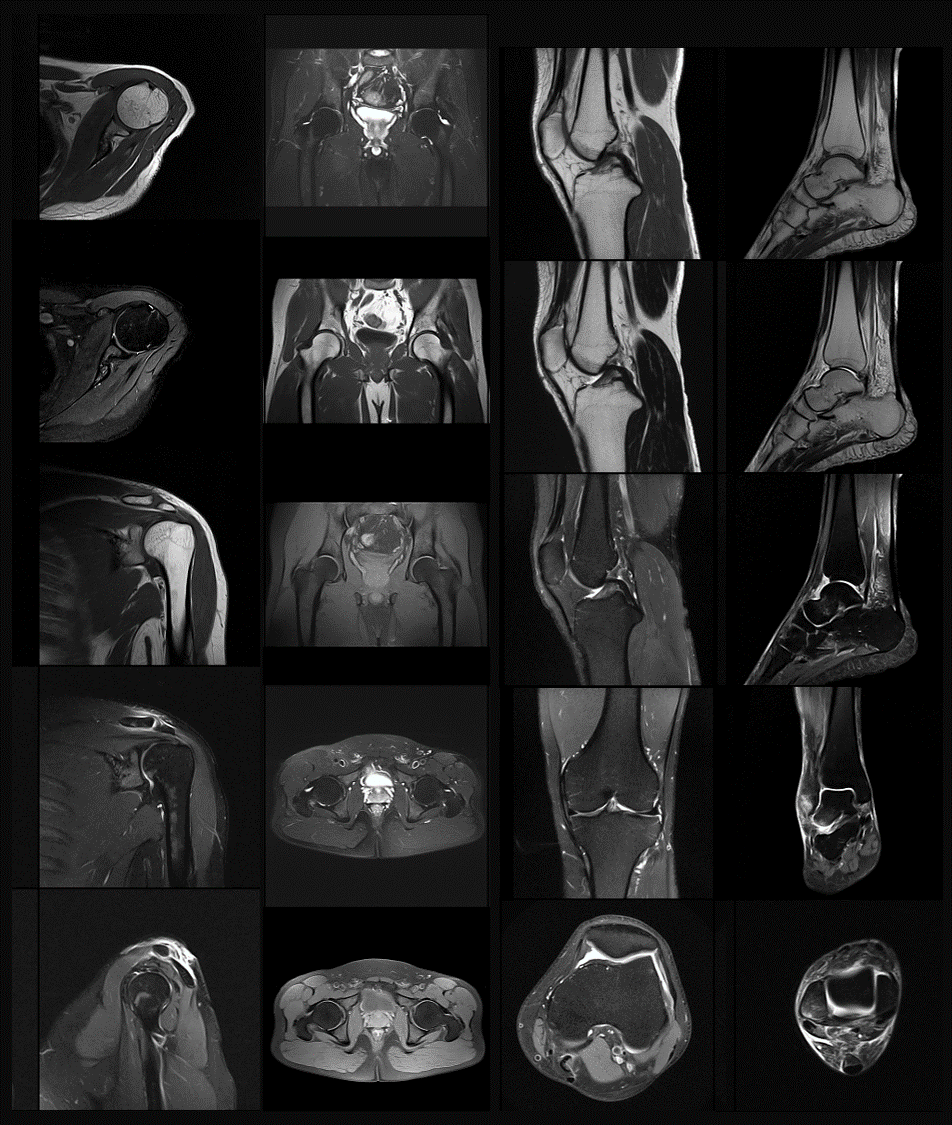

MR

骨肌系統

醫療科技事業部